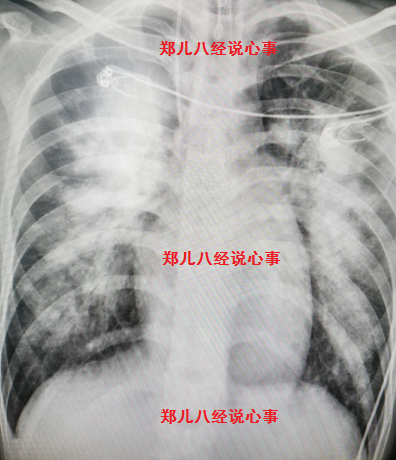

图1 胸部平片显示典型的双侧肺门蝶形影

很快锁定重症肺炎、肺水肿的原因可能是心源性。心肺听诊也有阳性发现:二尖瓣听诊区可闻及收缩期2~3级杂音,肺部有湿性啰音。经胸心脏彩超发现二尖瓣前叶脱垂并二尖瓣重度关闭不全。

明确心源性肺水肿、感染性心内膜炎、二尖瓣赘生物并重度关闭不全,加强利尿治疗同时启动手术程序。术中及术后病理证实为慢性心内膜炎。术后心肺功能好转,复查胸片双侧肺门蝶形影消失(图3)。

图3 术后胸片与图1胸片时间仅差4天,术后肺水肿迅速消失,胸片上典型的双侧肺门蝶形影消失